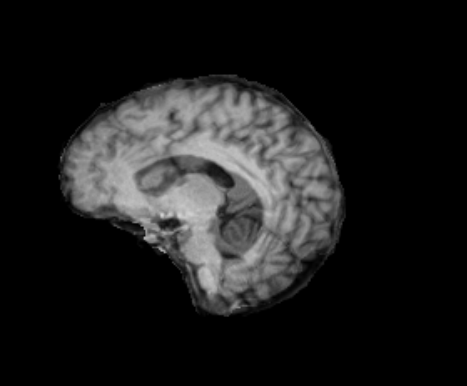

3.2.2 Robustness

In this experiment, we evaluate the robustness of Polaffini and the competing methods by computing a failure rate. We considered as potential outliers all cases for which the average Dice score over all regions after registration was below 0.34 (Z-score below -1.5, pooling Dices from all affine methods). All potential outliers were visually inspected to assess the reason behind the poor anatomical structure overlap score. All of them were clear failure cases, not just a residual misalignment to be expected after an affine registration. The failure counts for each method are reported in table 2. Almost all of the failure cases only occurred when registering with Flirt, mostly when subjects from the IXI dataset were involved. The most common failure type, showcased in Fig 6-a., consists of a local minimum where the frontal part of the moving brain is matched with the cerebellum of the reference one, a less frequent upside-down outcome is showcased in Fig 6-b. We suspect it is due to the fact that images from IXI have their axes ordered differently compared to the other two datasets and the template. However, since this information is contained in the header, it is unclear why Flirt could not handle the situation properly. Without the restriction of the angle search to , Flirt would give worse results (19 failure cases for subject-to-template and 61 for subject-to-subject). The only failure case using Anima for subject-to-subject is shown in Fig 6-c. For the rest of this section, we discard registrations if at least one of the methods has failed.

| reference | moving | moved | reference and moved | |

| a. | ukb_1154012-20252 | adni_AD-012-S-0720 | registered with Flirt | |

![]() |

|

| b. | ixi_165-HH-1589 | ukb_1145033-20252 | registered with Flirt | |

| c. | ixi_143-Guys-0785 | adni_MCI-003-S-6258 | registered with Anima-aff | |